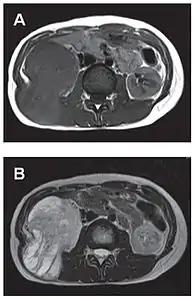

L'imagerie par résonance magnétique permet une exploration complémentaire dans certaines localisations. Elle est surtout réalisée pour les tumeurs du système nerveux central[8],[12],[43], du foie et du pelvis[31],[41]. Elle évalue mieux les différences de densité intra-tumorale et permet d'affirmer l'absence d'envahissement des tissus mous et des structures osseuses voisines[20]. Les tumeurs fibreuses solitaires ont un aspect d'isosignal en séquence T1 et d'hypersignal en T2, et se rehaussent après l'injection de gadolinium[31]. Cependant, dans le système nerveux central, elles ne présentent pas de critères caractéristiques permettant de poser un diagnostic de manière uniquement radiologique[12] et, en pré-opératoire, sont souvent confondues avec un méningiome[43].